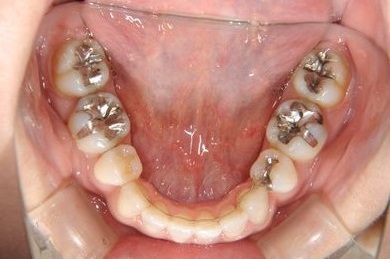

| 主訴 | 歯並び(乱ぐい歯、出っ歯)と歯の色が気になる。 | ||||||||||||||||||||||||||||||||

| 治療方針 | 左上の第一大臼歯がすでに抜歯され欠損の状態で来院されました。デンタルインプラント、あるいはブリッジで補綴するよりも、上あごが突出していること、乱杭歯があることより、矯正治療を第一選択としました。上下第一小臼歯を4本抜歯してその隙間を利用し、治療していきました。抜歯スペースをすべて効率的に利用したいため、上顎左右、下顎左側1本の計3本のインプラントアンカーを使用します。左上は第二大臼歯、智歯を利用しています。今後保定装置の針金は一生装着予定です。上顎の中切歯は左右とも人工的にかぶせものをしています。初診の歯牙変色がなくなり、審美的にもとてもよくなりました。 | ||||||||||||||||||||||||||||||||

| 治療内容 | インプラント矯正(唇側矯正ホワイト、審美ワイヤー、左右上顎第一小臼歯抜歯、上顎インプラントアンカー) | ||||||||||||||||||||||||||||||||